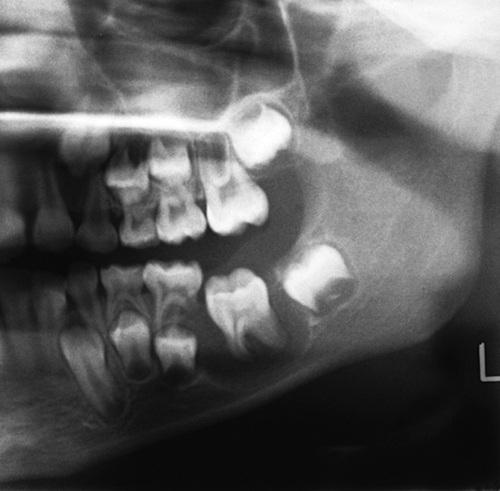

Well-circumscribed unilocular radiolucency superimposed on the roots of the mandibular first permanent molar. Periodontal probing revealed pocket formation on the buccal aspect.

buccal bifurcation cyst